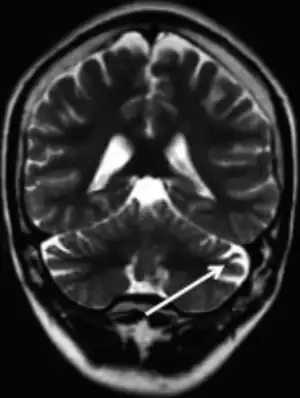

| MRI (adult) showing cerebellar atrophy in Dravet syndrome | |

The cause if often a genetic mutation in the SCN1A gene.[4] Around 90% of mutations newly occur during early development, rather then being inherited from a person's parents.[3] A family history of seizures is present in nearly half of cases.[8] Diagnosis is based on symptoms and genetic testing.[5] MRI of the brain is typically normal initially, though may show changes such as atrophy in some adults.[2]